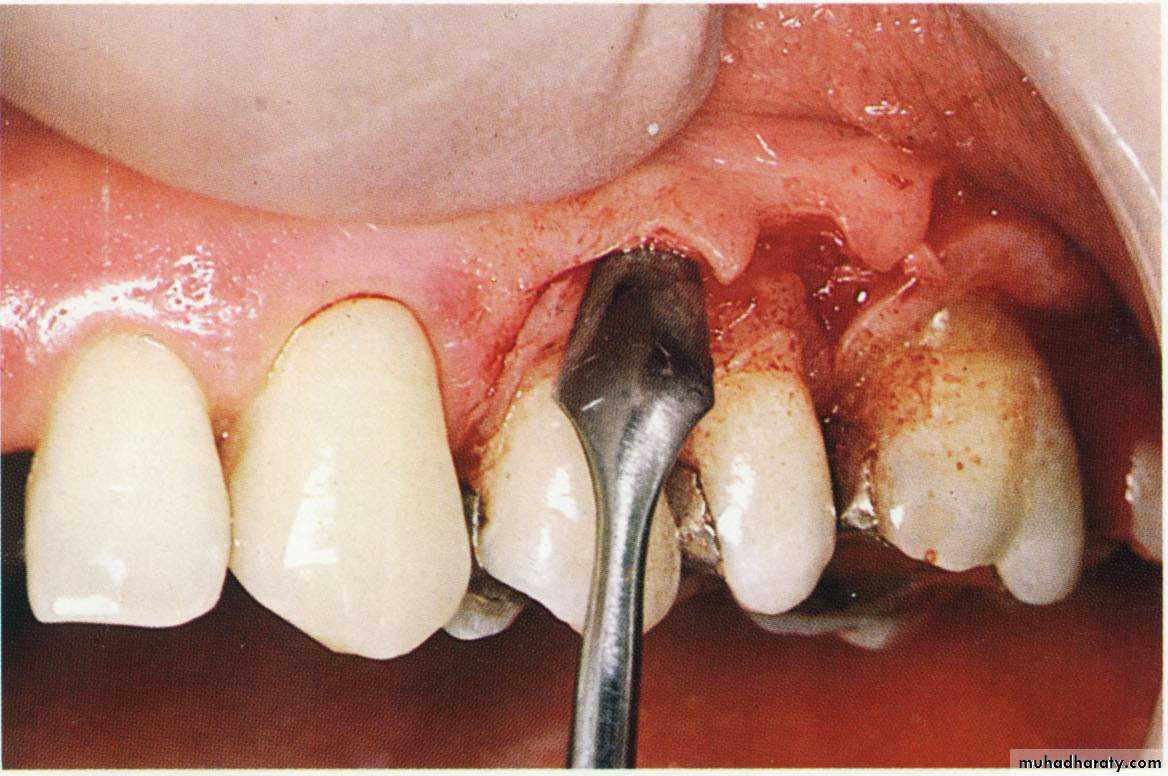

The minor alterations in gingival morphology usually termed gingivoplasty while the procedures that compromised a major amount of gingival tissues termed as gingivectomy.Goldman gingivectomy procedure:

1. Giving of local anesthesia.

2. Determination of the bleeding points by using the pocket depth marker.

Primary beveled incision, which carried out according to the bleeding points.

4. Secondary incision to separate the interproximal soft tissues form the

interdental periodonteum.5. Careful removal of the incised tissues by a curette or a scalar.

6. The bleeding can be controlled by a gauze pack inter proximally.

& performing of a careful scaling for the exposed root surface.7. Adjustment of the gingival contour & checking of the dentogingival area.

8. Dressing of the wound for (7 – 10 days).

9. Dressing removal & polishing.